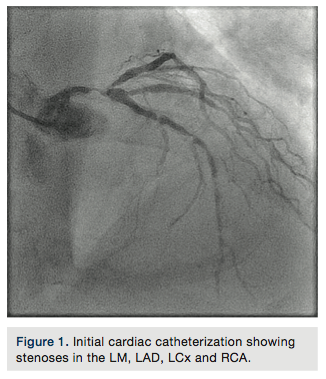

heaviness at rest, and severe resting shortness of breath. He was found to have pulmonary edema, with troponin I elevation (44 I.U), GFR=25ml/min, and hemoglobin of 9g/dl. Left ventricular ejection fraction (LVEF) by echocardiography was 25%, with severe anterior and lateral hypokinesia, moderate mitral regurgitation, and estimated right ventricular systolic pressure (RVSP)=55mmHg. Cardiac catheterization was performed and revealed a 90% distal eccentric calcified left main artery stenosis (Figure 1), tandem stenoses at the proximal, mid and distal left anterior descending artery (LAD), a 95% ostial calcified left circumflex stenosis, and severe diffuse disease in the proximal right coronary artery. No significant aortic stenosis was found. Pulmonary artery pressure was 70/30mmHg, with pulmonary capillary wedge pressure (PCWP)=20mmHg. Cardiac index, calculated using the Fick equation, was 1.9 l/min/m2.